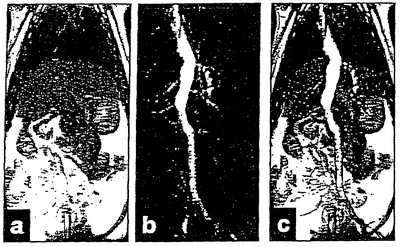

Способ параводородного переноса поляризации, как описано в WO 99/24080 (Nycomed Imaging AS), с использованием катализатора (PPh3)PhCl, был осуществлен с применением диметилового эфира малеиновой кислоты, меченного 13С в карбонильной группе (см. фиг.2). После поляризации поляризованное соединение было введено в качестве контрастной среды в вену хвоста крысы.

Концентрация и поляризация ядер 13С в болюсе, который был введен в крысу, составляли 150 мМ и приблизительно 0,3%, соответственно, и была осуществлена визуализация (см. фиг.1).

Изображения, показанные на фиг.1, были получены с применением сканера для животных BioMed, работающего при 2,4 Тл. Изображение, приведенное на фиг.1а, является протонным изображением и было получено с использованием стандартной последовательности импульсов спинового эха и без применения какой-либо контрастной среды. Параметры последовательности импульсов были следующими: TR/TE/d=3,3 мс/1,4 мс/ 5°, общее время сканирования 4:23 мин. Затем была получена доза гиперполяризованной контрастной среды. Резонансная частота была изменена на частоту, необходимую для осуществления визуализации 13C-изображения, и была проведена однократная RARE последовательность. Полное время сканирования составило 0,9 с, примененное время взаимного отражения (эха) составило 28 мс, а размер матрицы был 128×32. Полученное изображение приведено на фиг.1б. Ясно продемонстрировано полное отсутствие фонового сигнала. Это изображение было получено в виде проекции прямо через все животное, что демонстрирует возможность получения ангиограмм таким же образом, как при использовании рентгеновских лучей. На фиг.1в показано наложение 13С-изображения на водородное изображение.